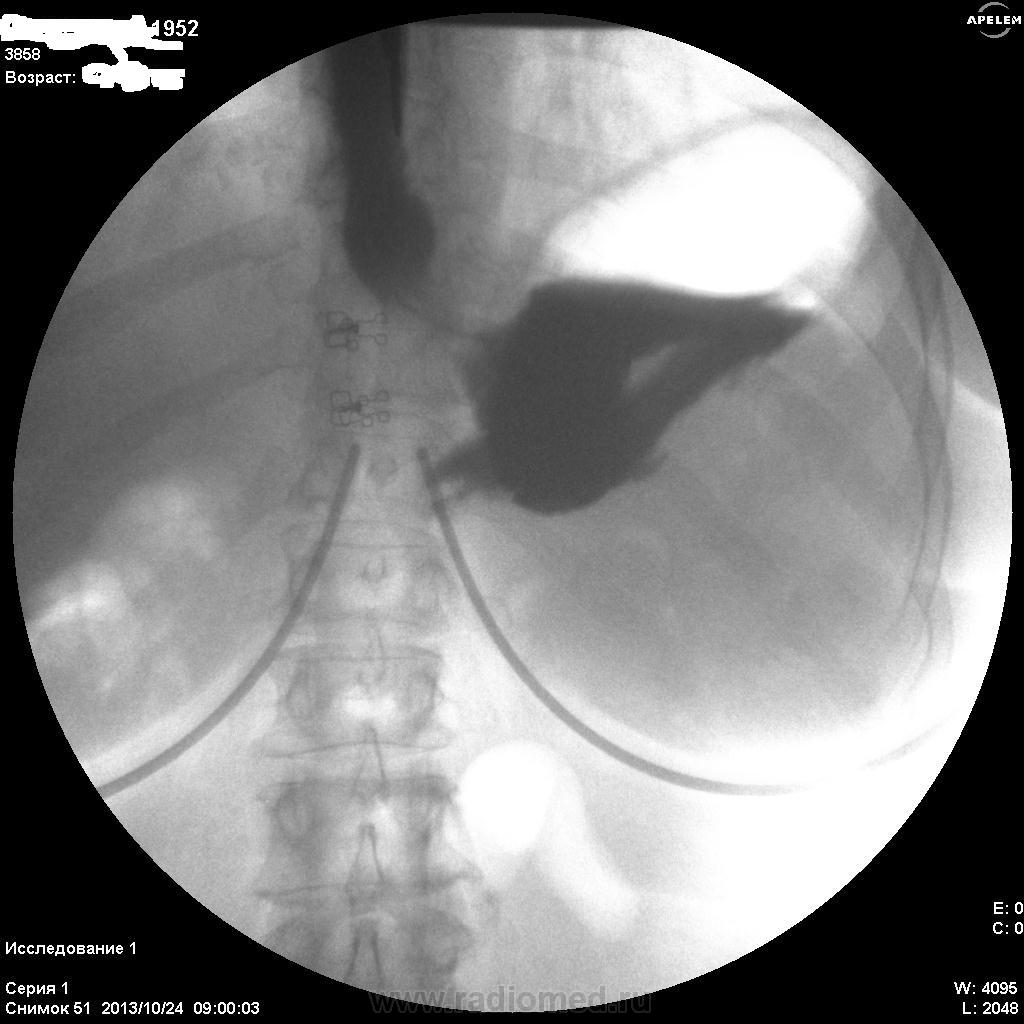

Пилорический отдел плохо выглядит, инфильтративная форма рака может быть. Лежа снимков нет? На что жалуется женщина? Лифчик немного мешает оценивать снимки))

Не сразу заметила дефект наполнения по большой кривизне, все не так с этим желудком

Необходимо уточнять состояние большой кривизны субкардиального отдела и тела (новообразование?), только ЭТИХ снимков явно мало...увы....

По-желудку - расположен косопоперечно, в гипертонусе. Впечатление не полного тугого наполнения. На большой кривизне могут быть и складки, плохо видно. На малой кривизне похоже на 2 ниши, ширина которых преобладает над глубыной, могут быть онкологические, но опять же куда они деваются на последнем снимке... Пилорический отдел либо конически сужен, либо не наполнен адекватно. В общем, можно просто предположить, либо это язвеная болезнь "хроническая" (отсюда деформация желудка и все остальное), либо это онкология (лимфома к примеру). Либо вообще такую картину дает гипертонус, усиленная перистальтика и малое количество контраста. Предложил бы искусственную гипотонию и бария не менее 200 мл.

Жалоб конкретных нет(так,что-то ноет).Еть отрывки кинопетли лёжа,но сегодня не смогу показать.Первый кадр здесь-стоя,потом-с поворотами налево и направо.Я собственно снимки не делаю,пишу кино.В "последующих сериях" деффект сохранялся,на компрессию не реагировал.

Как вариант, язва (или рубцово-язвенная деформация) по малой кривизне тела желудка с пальцевым вдавлением/"перстом указующим" по б/кривизне антрального отдела.

А поджелудочная (головка), так скиалогически далека от нормальности.